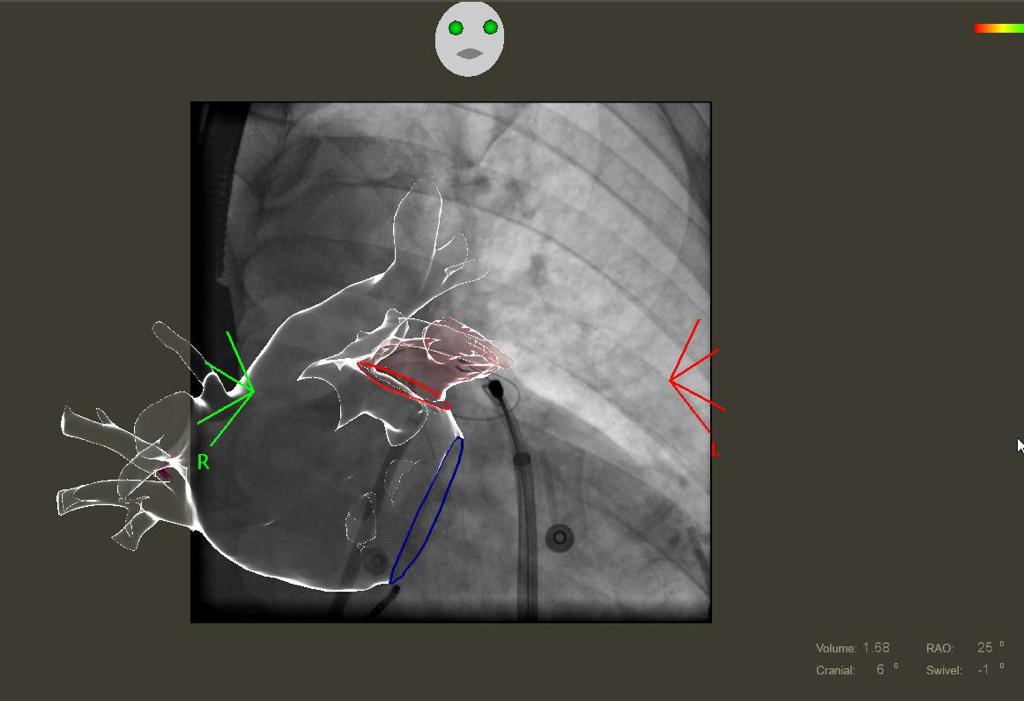

Il paziente operato al Mauriziano, affetto da fibrillazione atriale refrattaria a terapia ablativa convenzionale, presentava inoltre un rischio elevato tromboembolico, ma non poteva assumere farmaci anticoagulanti né antiaggreganti a lungo termine per elevato concomitante rischio di sanguinamenti. E’ stata pertanto eseguita una ablazione della fibrillazione atriale sia tradizionale che attraverso la superficie esterna, epicardica, del cuore, mediante un approccio mini-invasivo non chirurgico associato ad una legatura esterna epicardica, ma non chirurgica della auricola sinistra. La procedura è stata effettuata in corso di sedazione superficiale.

La combinazione delle due tecniche, utilizzata per la prima volta al mondo, ha consentito di ripristinare un regolare ritmo cardiaco ed abbattere sensibilmente il rischio di ictus cerebrale senza la necessità di sottoporre il paziente a terapia anticoagulante o antiaggregante a lungo termine, evitando in questo modo episodi di sanguinamento.

L’ablazione eseguita sulla superficie esterna del cuore, definita epicardica, consente infatti di accedere ad aree aritmogene che non possono essere raggiunte mediante l’approccio tradizionale dall’interno del cuore a causa dello spessore della parete cardiaca, migliorando di molto i risultati della procedura ablativa. La legatura epicardica della auricola sinistra, mai effettuata prima in Italia, consente di abbattere il rischio di ictus embolico legato alla fibrillazione atriale senza necessità di mantenere il paziente non solo in terapia anticoagulante, ma se richiesto anche in terapia antiaggregante. A differenza di tutti i sistemi utilizzati in precedenza infatti, questa metodica non prevede l’inserimento di alcun dispositivo permanente all’interno delle camere cardiache. Inoltre determina una esclusione anche elettrica della auricola che migliora ulteriormente il risultato dell’ablazione.